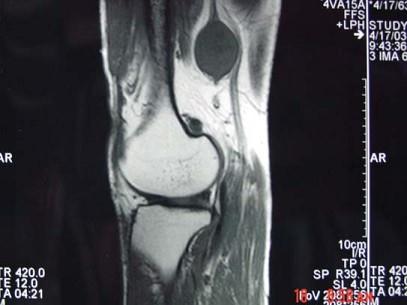

问题 男,48岁,腘窝上方疼痛2年余,呈持续性钝痛,且疼痛逐渐加重,曾以"结核”治疗无明显好转,体检腘窝上方肿胀,局部压痛,实验室检查均正常,请结合所提供的图像,选择最佳选项 ( )

选项 A、腘窝上方神经鞘瘤 B、腘窝上方脓肿 C、腘窝上方血管瘤 D、腘窝上方肌腱神经纤维瘤 E、腘窝上方囊肿

答案 D